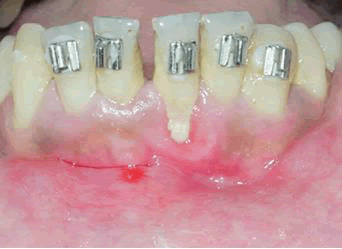

Gingivitis/gingival enlargement: Gingival inflammation is the instant clinical tissue response that can be appreciated in almost all orthodontic patients. Orthodontic treatment is capable of creating local changes in the oral microbial ecosystem and changing the composition of the bacterial plaque qualitatively and quantitatively. Generally, plaque accumulates subgingivally, which leads to gingival inflammation (Figure 3). It is immediately observed after fixed appliance therapy, inhibiting the maintenance of oral hygiene [11].

JDS-showing

Figure 3: Picture showing gingivitis and gingival enlargement.

Zachrisson and Zachrissonn, et al stated that even after sustaining excellent oral hygiene, patients usually experience mild to moderate gingivitis within 1 to 2 months of appliance placement. It is transient and does not lead to any additional complications, such as loss of gingival attachment except for 10 % of adult patients.

The interproximal areas are often more affected than the facial areas and posterior teeth more than anterior teeth.

One of the most common complications with gingivitis associated with Orthodontic treatment is gingival enlargement. The affected tissue generally shows swelling and may bleed when slightly probed. According to Kloehn and Pfeifer, et al. posterior teeth are four times more affected than incisors and canines.

Enlargement is because of mechanical irritation by bands, more on posterior than on anterior teeth. Cement-induced chemical, food impaction, because of the proximity of the arch wires to the soft tissues, and poor oral hygiene maintenance. The interdental region is frequently affected compared with the facial aspect of the gingiva margin. Zachrisson, et al. found that the mandibular incisor region had the highest risk for the development of gingival enlargement.